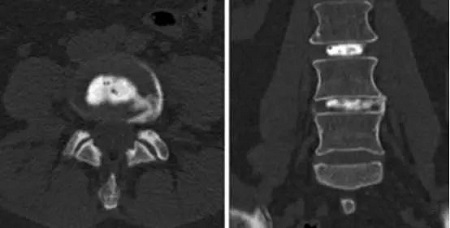

CT軸位和前后位顯示L4-5間盤造影和血小板注射。